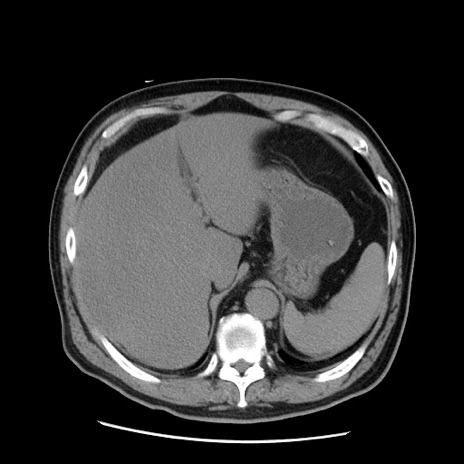

症例20(横断像)

【症例】 60歳代男性

【主訴】 腹部膨満、嘔吐

【現病歴】5日前頃より倦怠感を認め食事量減少し4日前の朝嘔吐、食事摂取困難となった。 3日前近医受診し点滴施行され整腸剤などを処方された。 当日他院を受診し、腹部膨満著明、炎症反応の上昇(CRP10.8、WBC11200)あり、紹介受診となる。

【身体所見】 意識JCS1 受け答えがはっきりしないBP 111/57mHg、 P 67bpm、、BT35.2°C、SpO2 97%(RA)、 腹部:膨隆、打診で鼓音あり、全体的に圧痛有り、腸蠕動音(-)、反跳痛ははっきりせず。

【データ】WBC 11400、CRP 14.20